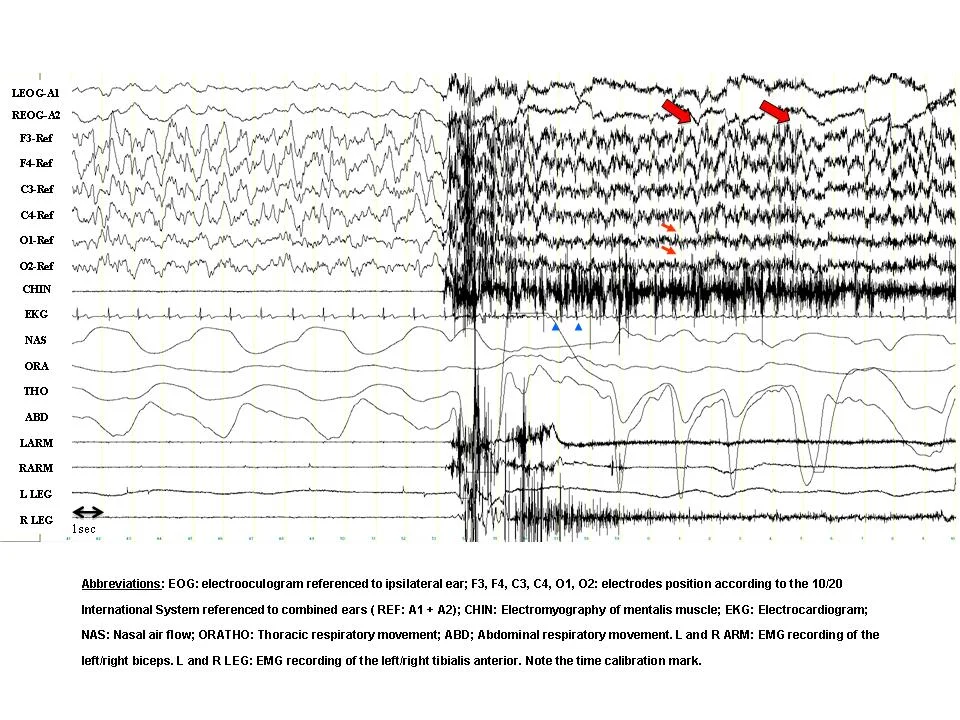

In this example, the first half of the window shows normal Stage N3 delta slow-wave sleep. At about half-way through, there is a sudden change in the EEG brain wave activity, shifting the patient from neurological sleep to a state of wakefulness.

In this example, this patient is experiencing sleep apnea episodes of breathing pauses. The CO2 monitor shows increasing carbon dioxide as the SaO2 monitor shows plummeting oxygen desaturations and hypoxia. In the Chin and EEG brain wave activity we see the patient's brain is briefly waking the patient up with corresponding arousals in response to the sleep apnea. And yet, after each arousal and airway opening, the patient falls right back asleep, the sleep apnea resumes again, and another corresponding arousal occurs. This sleep apnea severity is likely responsible for significant sleep architecture disruption, paucity (or reduced) restorative sleep, daytime fatigue and sleepiness, reduced concentration at work or when driving, and many other significant health risks. The repeated loss of oxygen and increased carbon dioxide also stress the heart and increase hypertension, diabetes, heart attack, and stroke risk factors.

In this example, the patient is experiencing a sleep apnea episode as indicated in the flat line. Once the flat line suddenly resumes breathing with the opening of the airway, the EEG brain waves above indicate a sudden and temporary shift from neurological sleep to neurological wakefulness lasting only a few seconds. The patient then falls back asleep, not realizing that they just briefly awoke. This patient's sleep apnea severity likely wakes the patient from sleep hundreds of times per night, violently disrupting the sleep architecture and potentially reducing the patient's restorative sleep.